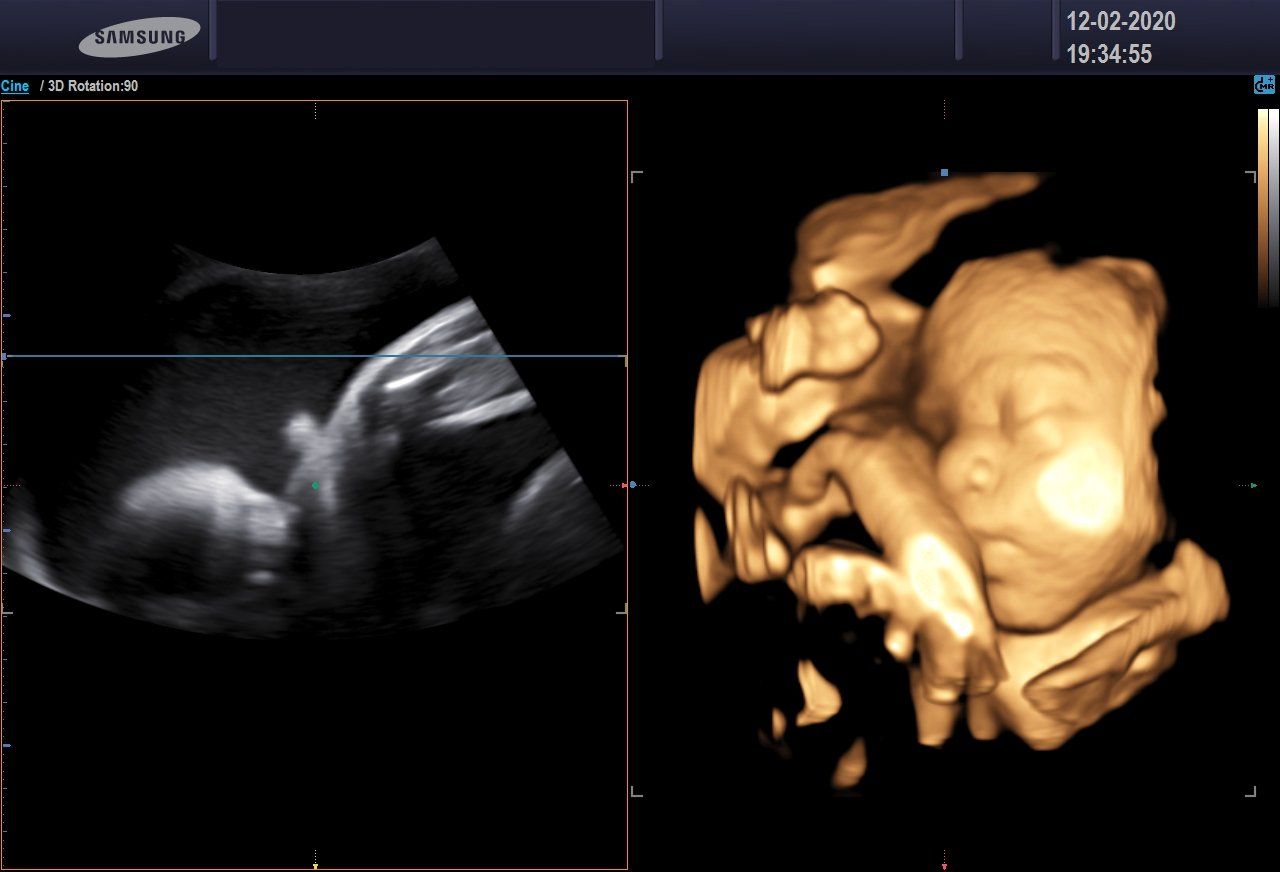

Ecografia 3D/4D

L'ecografia 3D consente di ottenere delle immagini statiche, non in movimento, ma in pratica delle foto delle fattezze del feto.